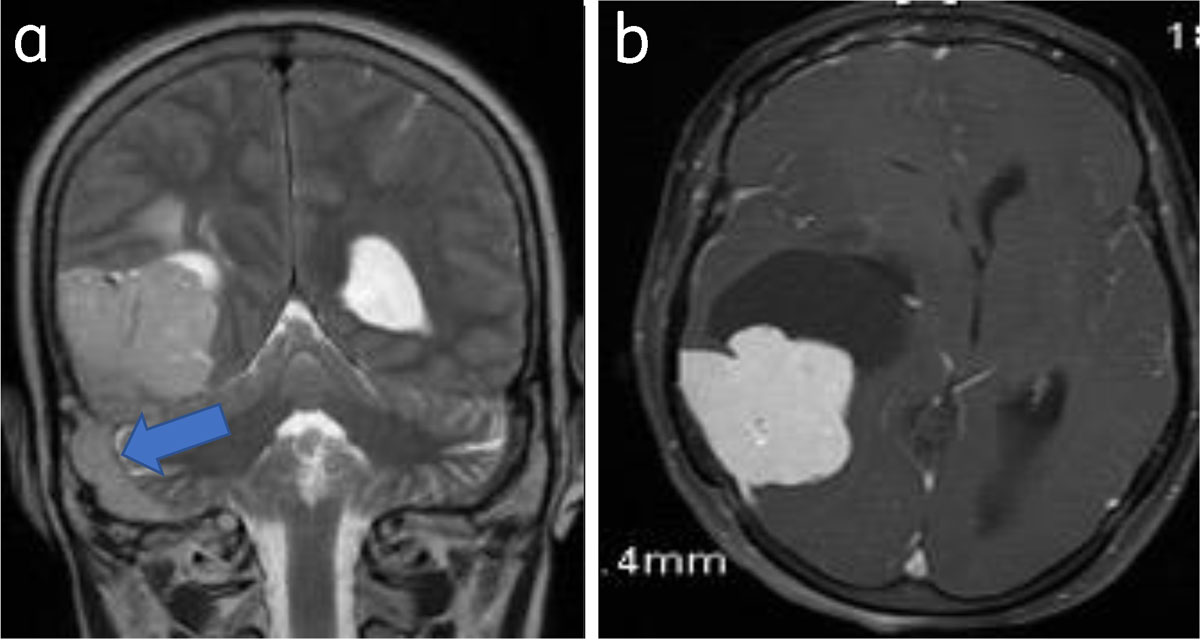

Figure 11

Meningioma with venous sinus invasion: Coronal T2WI (a) and axial (b) post-contrast images show right parieto-occipital meningioma with right sigmoid sinus invasion (arrow).